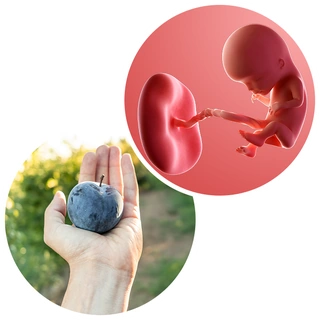

در هفته دوازدهم بارداری، نوزاد شما تقریباً به اندازهی یک لیموترش کوچک است — حدود ۷ سانتیمتر طول و حدود ۱۵ گرم وزن دارد. او حالا دیگر شبیه یک انسان واقعی است و در حال تمرین نفس کشیدن، بلعیدن و حتی سکسکه کردن است!

چهرهی جنین در این هفته شکل واضحتری گرفته است.

– سر او که پیشتر نصف طول بدنش بود، اکنون فقط یکسوم بدنش را تشکیل میدهد.

– پلکها، بینی، لب بالا و گوشها کاملاً شکل گرفتهاند.

– حرکات ظریف دستها و پاها شروع شدهاند، هرچند هنوز شما آنها را احساس نمیکنید.

درون بدن کوچک او، اتفاقات مهمی در حال رخ دادن است:

– خون در بند ناف جریان دارد و اکسیژن و مواد مغذی را از طریق جفت به جنین میرساند.

– کلیهها فعال شدهاند و ادرار تولید میکنند.

– سیستم عصبی در حال بلوغ است و عضلات به سیگنالهای مغزی پاسخ میدهند.

برخی از پژوهشها نشان دادهاند که در همین زمان، میتوان تفاوتهای ابتدایی در ویژگیهای رفتاری و شخصیتی جنین را مشاهده کرد؛ برای مثال، بعضی نوزادان در این سن انگشت شست خود را میمکند یا تحرک بیشتری دارند.

حرکات او هنوز غیرارادی هستند، اما رفتهرفته هدفمندتر میشوند.

اگر میتوانستید در این لحظه دست او را لمس کنید، احتمالاً واکنش نشان میداد و انگشتهای کوچکش را میبست — حرکتی که در چند هفته آینده هنگام سونوگرافی قابل دیدن خواهد بود.